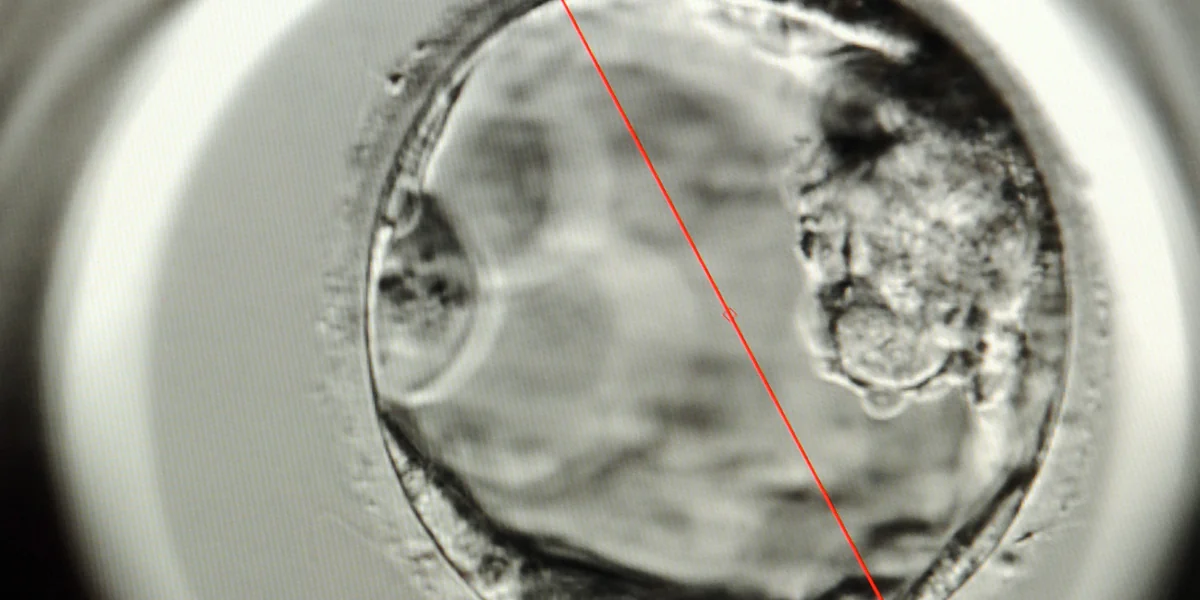

Ein fünf Tage alter Embryo – rechts neben der roten Linie. Foto: dpa